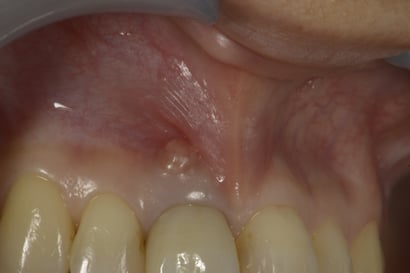

前歯の歯肉に近い場所に”おでき”のようなものができています。これを瘻孔(ろうこう、サイナス・トラクト)といいます。

歯の根の”破折”や”ヒビ”がある時にもできますが、状態が違います。ここでの瘻孔は、神経がない歯の根の先に炎症が生じ(根尖病巣)、それが歯の根を支える(歯槽骨)と歯肉を経由(瘻管形成)して、出口がこの瘻孔となります。当院では、根尖病巣が原因で生じた瘻孔は、1回の治療後、約3日〜1週間で消失させることが可能です。

この症例では、治療後3日で瘻孔は消失しました。

歯の神経を除去する治療をしていない歯であっても、何らかの原因で歯髄が死んでしまい、同様に瘻孔形成をすることもあります。